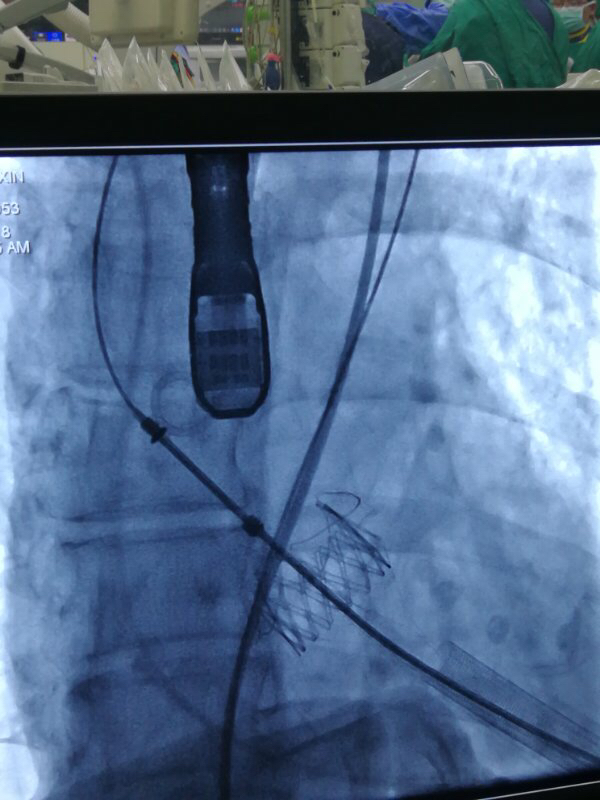

图片说明:人工瓣膜释放。

图片说明:人工瓣膜释放完成。

术中,在TAVI心脏手术团队的协作下,首先在患者心尖部位开一小孔,然后操控一根细长的输送鞘,将人工生物心脏瓣膜送入患者心腔。在造影屏幕监视下,新瓣膜被准确定位和放置于病变主动脉瓣位置。原来的心脏泵血“阀门”因关不紧“漏水”,新瓣膜“安装”完毕后,就像一扇运行良好的新“阀门”,一张一合地开始工作了。